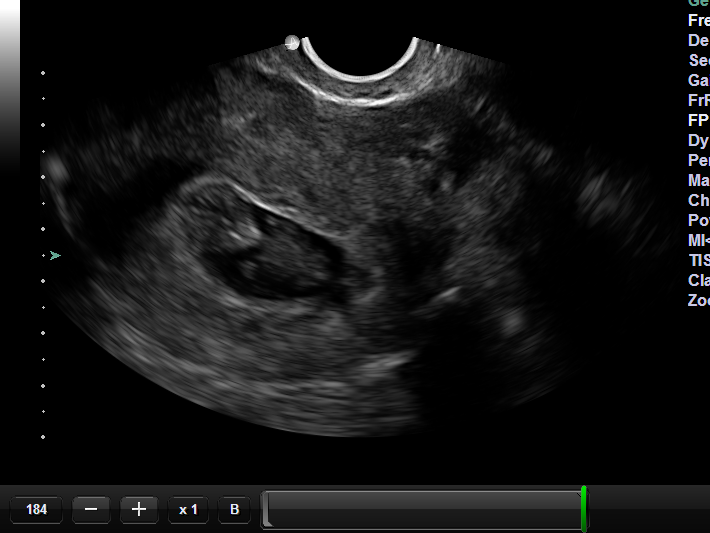

When the GC went in for the first ultrasound, there was a gestational sac, but no embryo could be seen. The technician said it was early yet. It was only just 6 weeks, so not unusual to miss something so tiny. Both the surrogate and parent were left feeling tentative, but hopeful. Another ultrasound was scheduled the following week. The repeat ultrasound showed an empty sac. No heartbeat, no baby.

Today, this sweet, special, wonderful woman got to make the most amazing phone call. There on the ultrasound was a 10-week old fetus, very much there and alive and swimming around in that once empty sac.